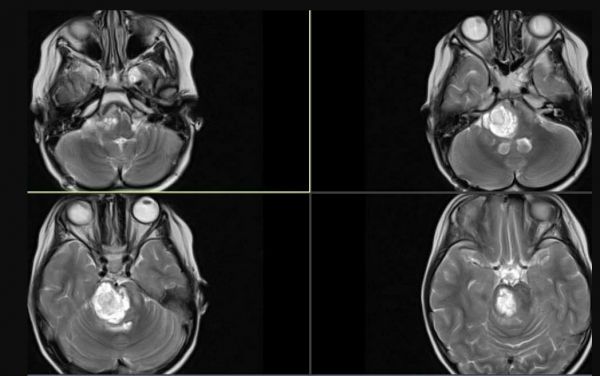

Εγκάρσιες τομές Μαγνητικής Τομογραφίας ασθενούς 6 ετών με ΔΔΓΓ